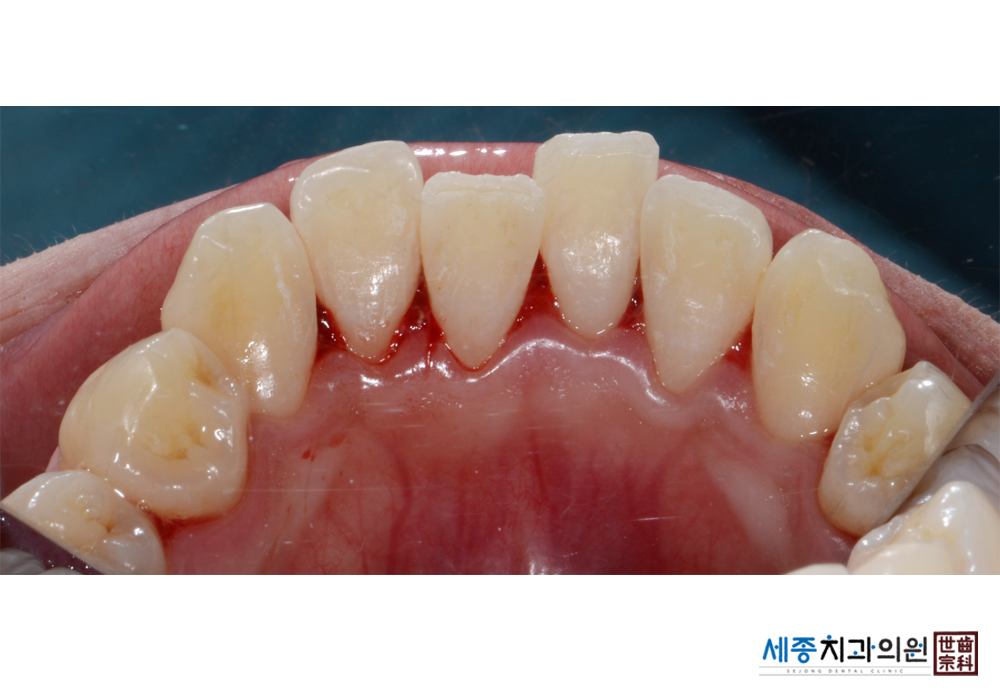

[스케일링] 치주질환 예방 스케일링 치료

치료전 : 2019-01-04

가글마취&저주파 스켈러를 사용한 스케일링